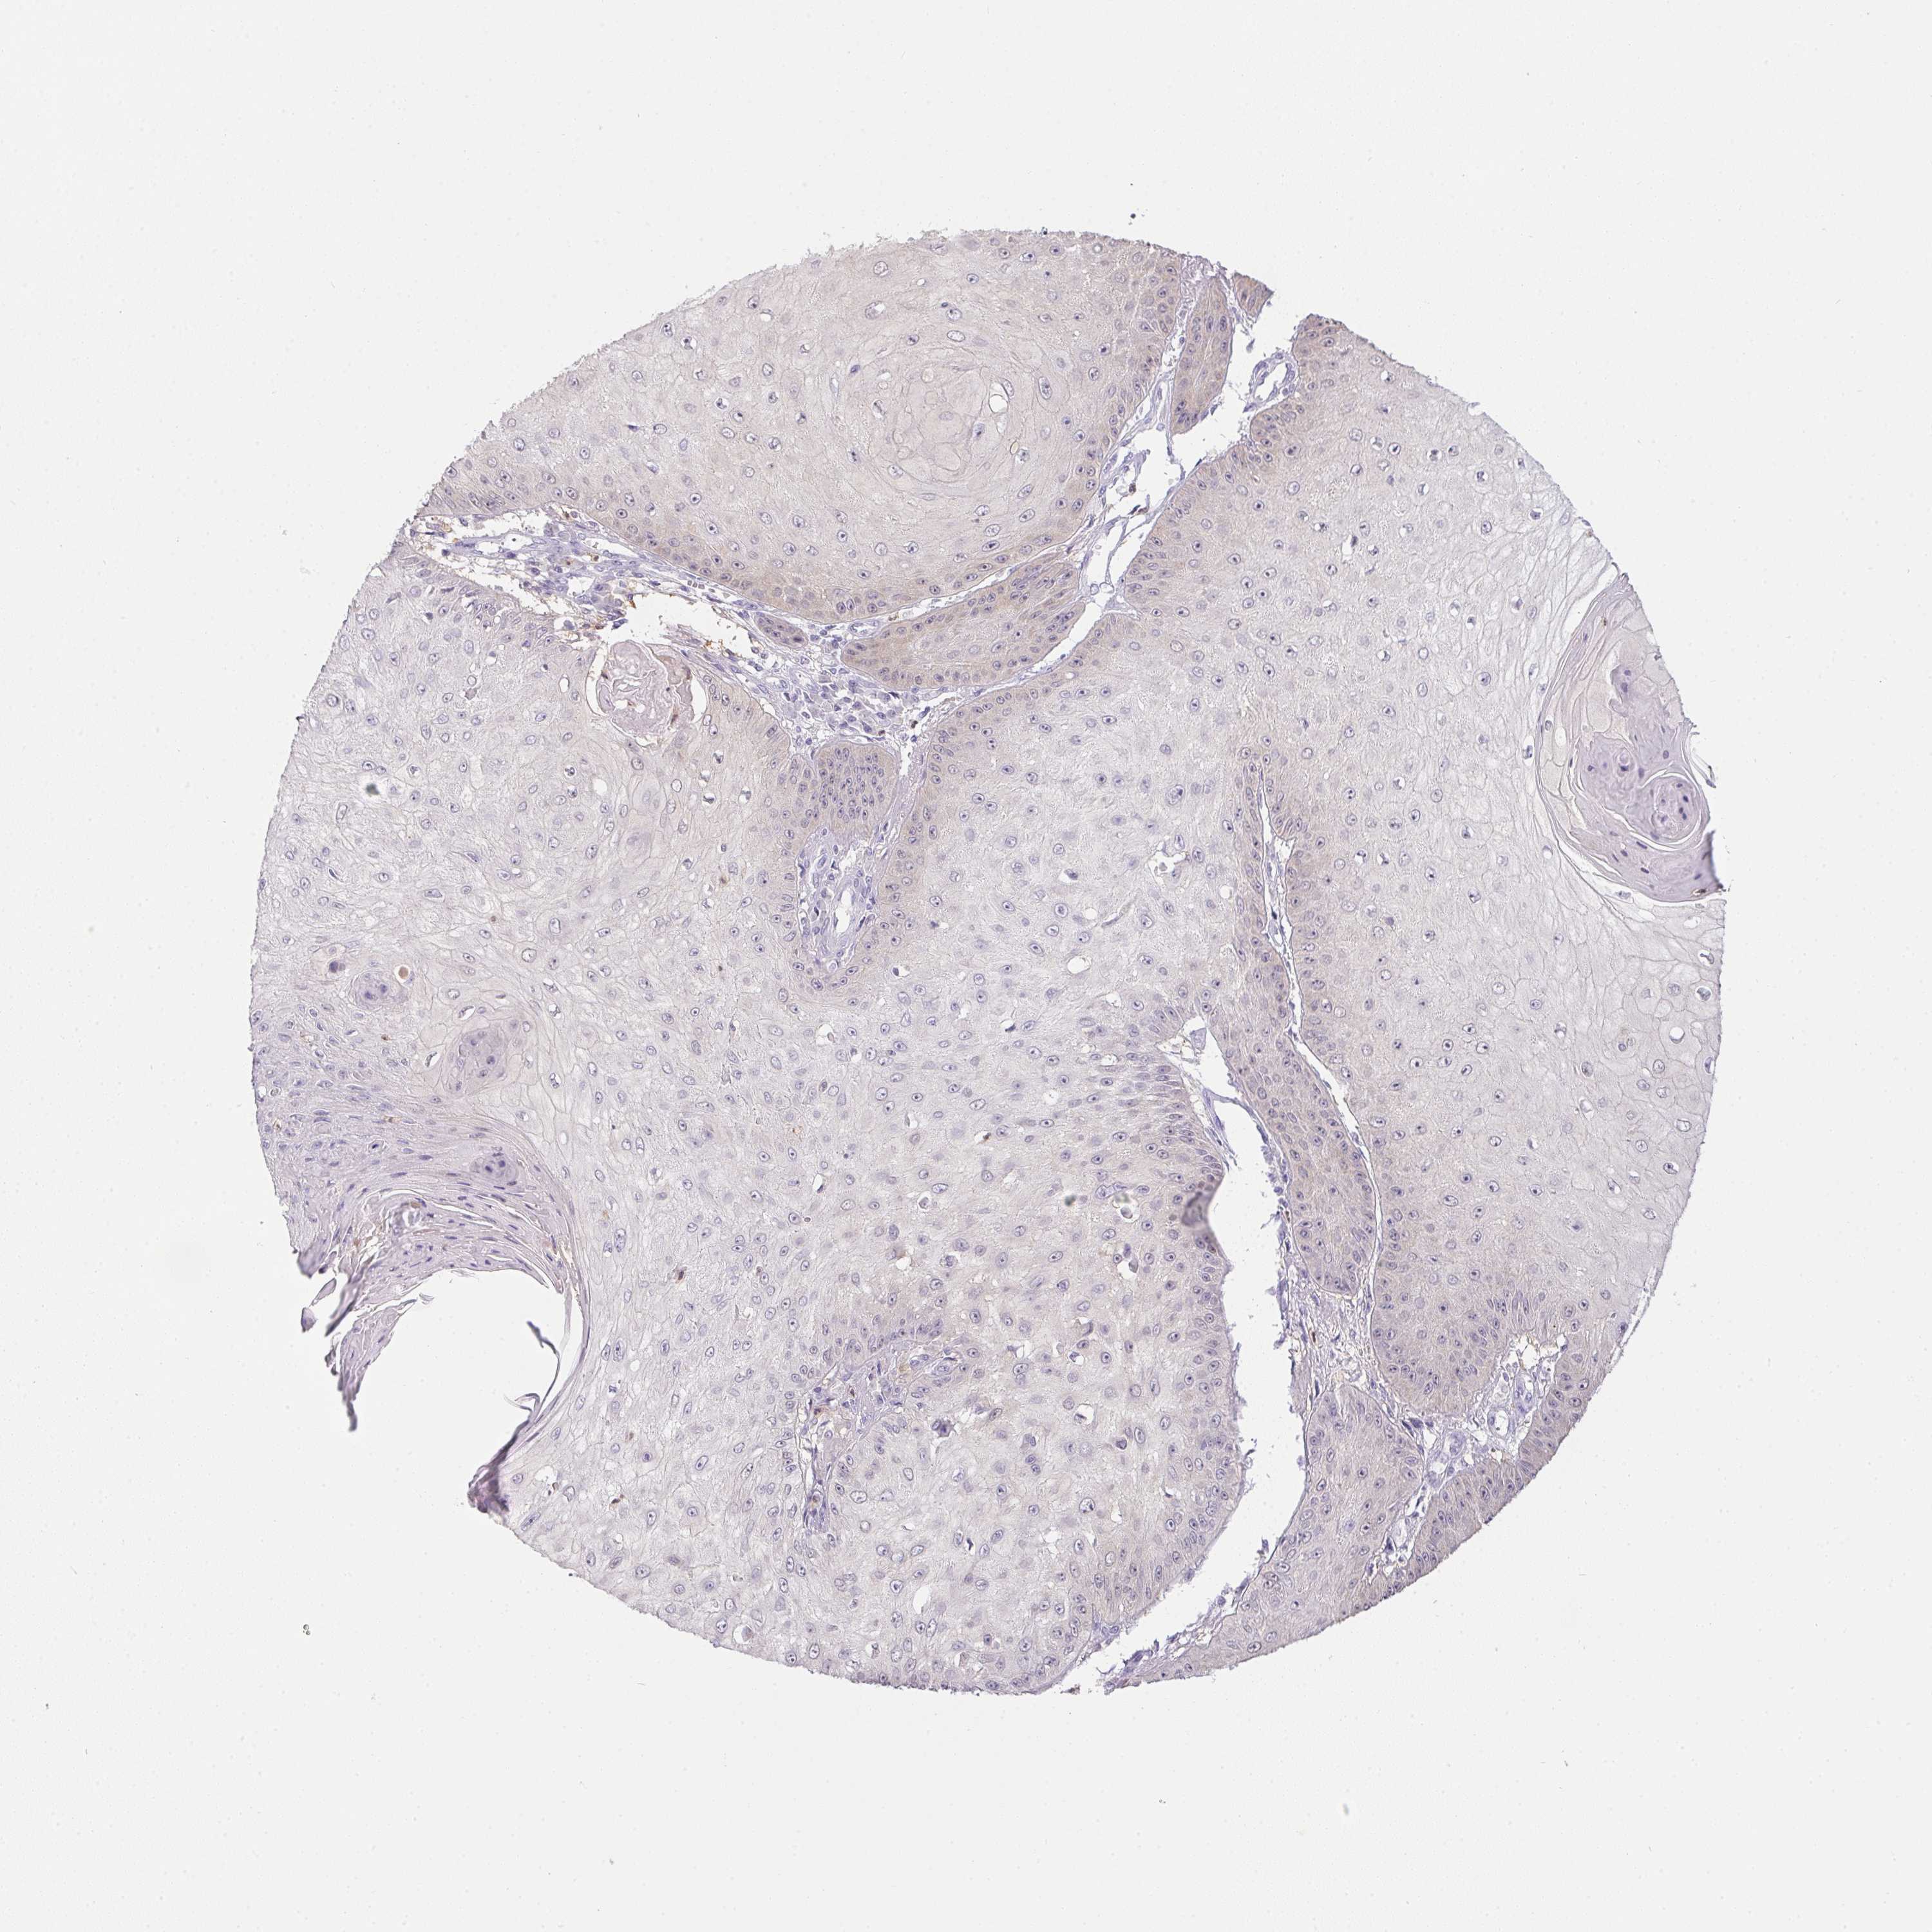

Basal cell and squamous cell cancer

SKIN CANCER - Protein expressioni

A mouse-over function shows sample information and annotation data. Click on an image to view it in a full screen mode. Samples can be filtered based on level of antibody staining by selecting one or several of the following categories: high, medium, low and not detected. The assay and annotation is described here.

Antibody stainingi

Antibody staining in the annotated cell types in the current human tissue is reported as not detected, low, medium, or high, based on conventional immunohistochemistry profiling in selected tissues. This score is based on the combination of the staining intensity and fraction of stained cells.

Each image is clickable and will lead to virtual microscopy that enables deeper exploration of all samples and also displays staining intensity scores, fraction scores and subcellular localization as well as patient and tissue information for each sample.

Antibody HPA041445

Staining

High

Medium

Low

Not detected

Intensity

Strong

Moderate

Weak

Negative

Quantity

>75%

75%-25%

<25%

None

Location

Nuclear

Cytoplasmic/membranous

Cytoplasmic/membranous,nuclear

Basal cell carcinoma

Squamous cell carcinoma, NOS